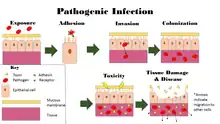

Pathophysiology

There is a general chain of events that applies to infections, sometimes called the chain of infection[15] or transmission chain. The chain of events involves several steps – which include the infectious agent, reservoir, entering a susceptible host, exit and transmission to new hosts. Each of the links must be present in a chronological order for an infection to develop. Understanding these steps helps health care workers target the infection and prevent it from occurring in the first place.[16]

Colonization

Infection begins when an organism successfully enters the body, grows and multiplies. This is referred to as colonization. Most humans are not easily infected. Those with compromised or weakened immune systems have an increased susceptibility to chronic or persistent infections. Individuals who have a suppressed immune system are particularly susceptible to opportunistic infections. Entrance to the host at host–pathogen interface, generally occurs through the mucosa in orifices like the oral cavity, nose, eyes, genitalia, anus, or the microbe can enter through open wounds. While a few organisms can grow at the initial site of entry, many migrate and cause systemic infection in different organs. Some pathogens grow within the host cells (intracellular) whereas others grow freely in bodily fluids.[17]

Disease

Disease can arise if the host's protective immune mechanisms are compromised and the organism inflicts damage on the host. Microorganisms can cause tissue damage by releasing a variety of toxins or destructive enzymes. For example, Clostridium tetani releases a toxin that paralyzes muscles, and staphylococcus releases toxins that produce shock and sepsis. Not all infectious agents cause disease in all hosts. For example, less than 5% of individuals infected with polio develop disease.[24] On the other hand, some infectious agents are highly virulent. The prion causing mad cow disease and Creutzfeldt–Jakob disease invariably kills all animals and people that are infected.[25]